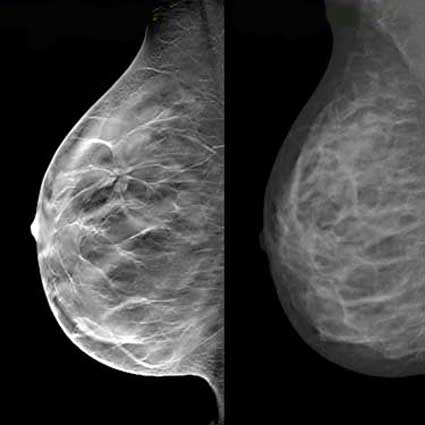

علیرغم تردیدهای گذشته دربارة نقش مثبت ماموگرافی بررسیهای جدید که توسط پزشکان آلمانی انجام شده است نشان دادهاند که ماموگرافی میتواند مرگ ناشی از سرطان پستان در زنان 75-50 ساله را به نصف کاهش دهد.

این تحقیقات نشان دادهاند که زنان 75-50 سالهای که حداقل 3 بار ماموگرافی انجام دادهاند 49 درصد کمتر به علت این بیماری میمیرند در برنامة فوق زنان 75-50 ساله هر دو سال یکبار تحت ماموگرافی قرار گرفتند.

بیشترین سود برای زنان 75-70 ساله بود که سبب 84 درصد کاهش در مرگ ناشی از سرطان پستان شد.